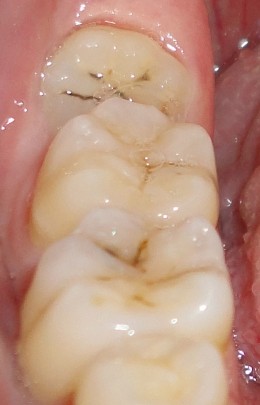

1 、智齿有蛀牙的情况:

如果智齿出现了蛀牙的情况的话,是要马上拔除的,智齿是一个比较容易发生蛀牙的部位,主要是其位置比较靠近里面,我们平时刷牙很难清洁到的缘故,所以容易产生蛀牙。

(3)第二磨牙龋坏:向前倾斜的阻生智齿,因经常在邻牙间积存食物,易发生邻牙(下颌第二磨牙)龋坏。